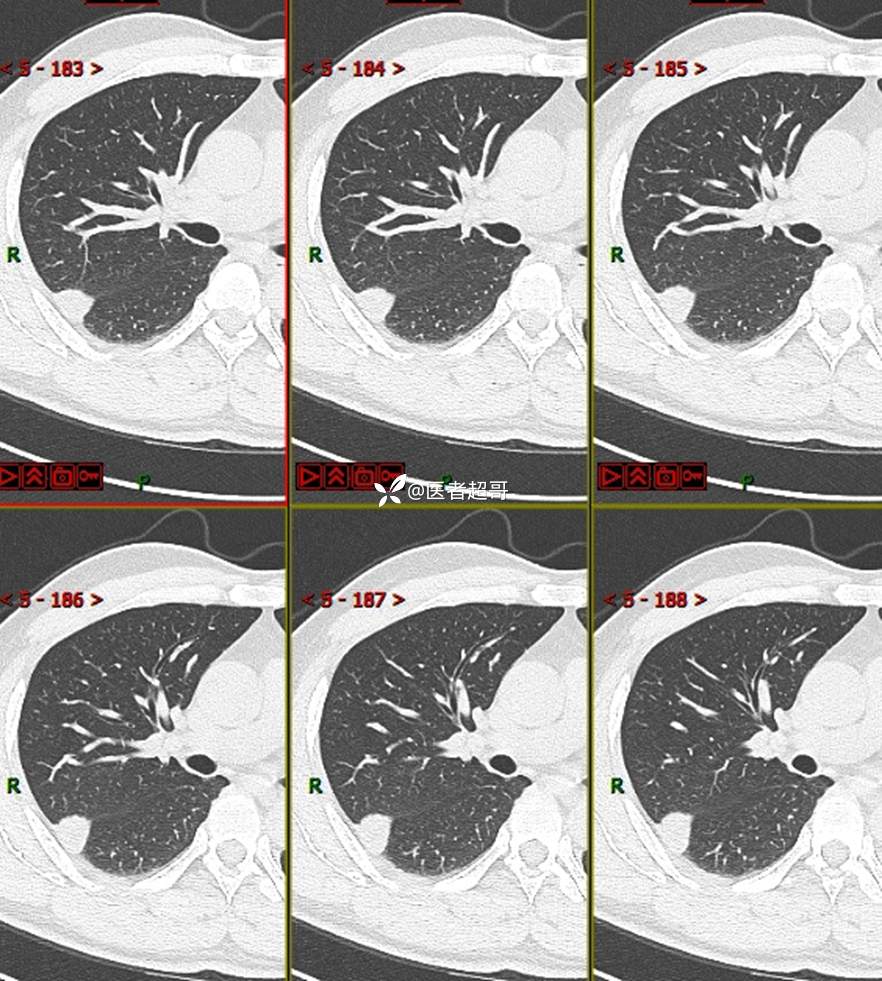

现病史:患者1年余前于体健中心行胸部X片发现右上肺叶密度增高影,无明显咳嗽,咳痰,无痰中带血及咯血,无胸痛及胸闷、气短,无发热、盗汗及全身乏力。无头痛、头晕,无腹痛、腹胀及恶心、呕吐,无声音嘶哑及呛咳,未行特殊治疗。后患者定期复查胸部CT,未见明显变化。2023-2-6患者于我院复查胸部CT:右肺上叶、下叶交接处胸膜下见实性结节影,最大截面约2.6cm×1.4cm,较前增大,建议行手术治疗。今为求进一步诊治,遂来我院就诊,门诊以“肺肿物”收入我院,患者自发病以来,神志清,精神可,饮食可,睡眠良好,大小便正常,近期体重未见明显增减。